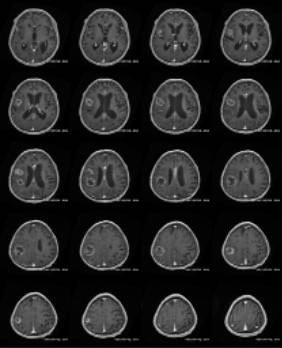

![]() 術前MRI